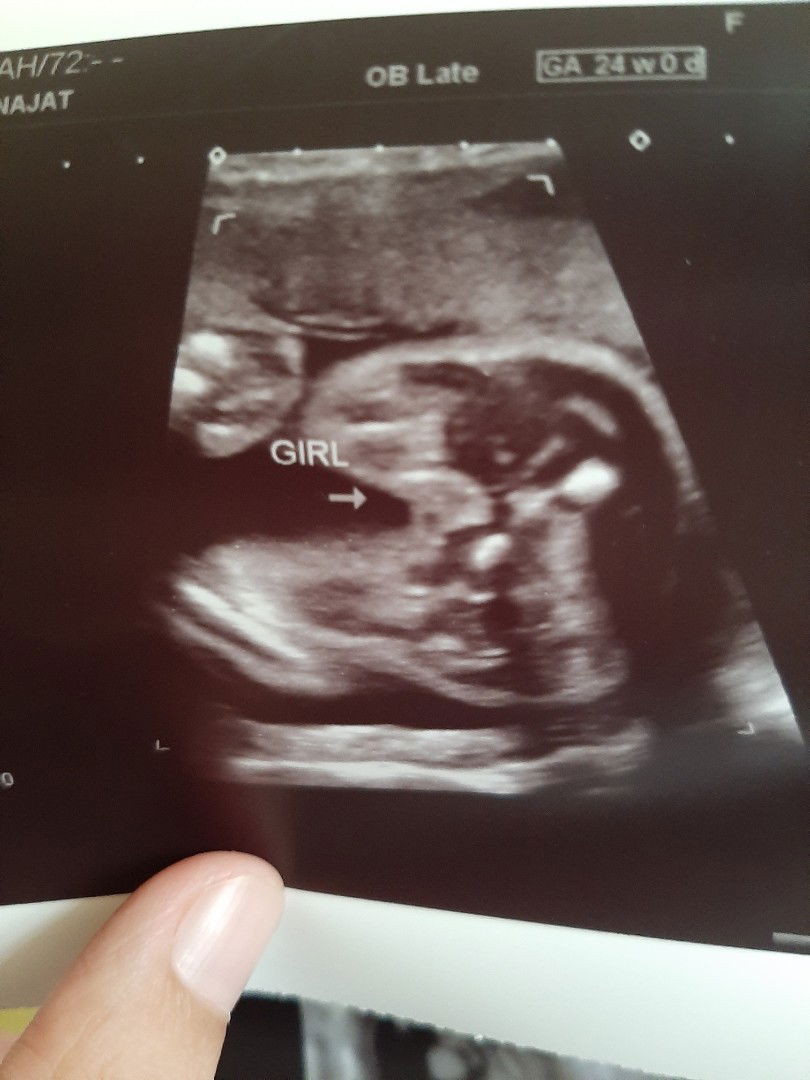

jantina baby

Hai ibu2, saya ada buat detail scan masa 24 weeks haritu.. ibu2 nampak girl ke boy mcmni?? Xkisah pn mane2, sje tanye pendapat sebab selalu baca scan lain keluar lain kn.. selalu detail scan ni memang tepat ye? #komenbaik2 #mohonjangankecam